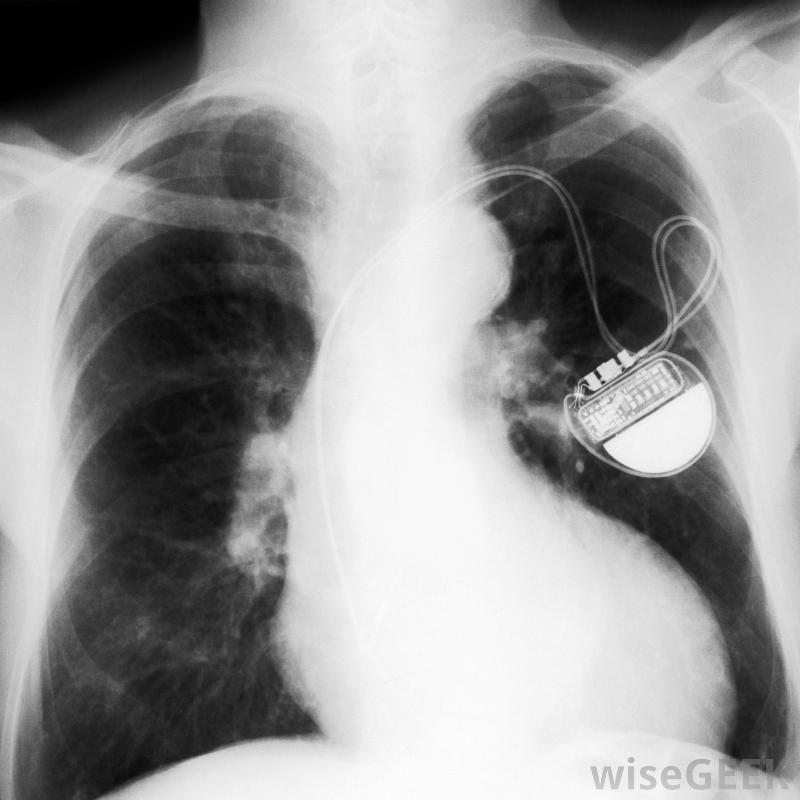

起搏器導線,也叫導線,是一根細線,一端與設備的發電機相連,另一端與心臟相連。每個起搏器可能有兩條或兩條以上的導線連接到右心房和右心室,有時還連接到左心室。導線的一端有一個電極,電極與心臟相連,以獲取心臟的自然電脈沖并將這些信息發送回發生器。心律失常的患者可能需要起搏器的幫助起搏器主要有三種類型。一種是用起搏器導線將發生器連接到右心室;另一種是將導線連接到右心室和心房,第三個將發生器連接到左心室和右心室以及右心房,使用哪種類型的起搏器取決于患者的情況以及哪種類型的起搏器是理想的。起搏器永久性地監測心房和心室的心臟節律。起搏器導線有幾種形式,雖然大多數是由金屬制成的,并具有某種絕緣涂層。有些采用螺旋式設計,而另一些則在一端有小尖頭連接到機身上。電線可以是直的、窄的,或者是"J"形或類似形狀,以便更有效地融入中庭許多起搏器使用一組導線來連接心臟的各個區域。具有旋入機制的導線在植入后能夠很快保持原位。然而,那些帶有尖齒的起搏器,通常更準確地定位心臟不規則。帶有螺絲裝置的導線更常見,但醫生將最終判斷每個患者需要哪種類型的起搏器導線。在放置過程中,起搏器導線插入胸部左上角的靜脈,與放置起搏器的位置相同。醫生通常使用透視鏡(一種X光片)來觀察導線穿過靜脈并進入心臟的正確位置。這通常被認為是一種小手術,而且病人一般不需要全身麻醉。手術通常在診所或醫生辦公室進行。起搏器導線發生故障的情況非常罕見,因為它們的設計相對簡單。更常見的是起搏器口袋可能會發生感染,而且整個系統都會被更換。很少有特定型號的起搏器或導線會因為設計或功能錯誤而被召回。偶爾需要向醫生咨詢以確保設備正常工作。當電池電量不足時,每五到十年更換一次起搏器。